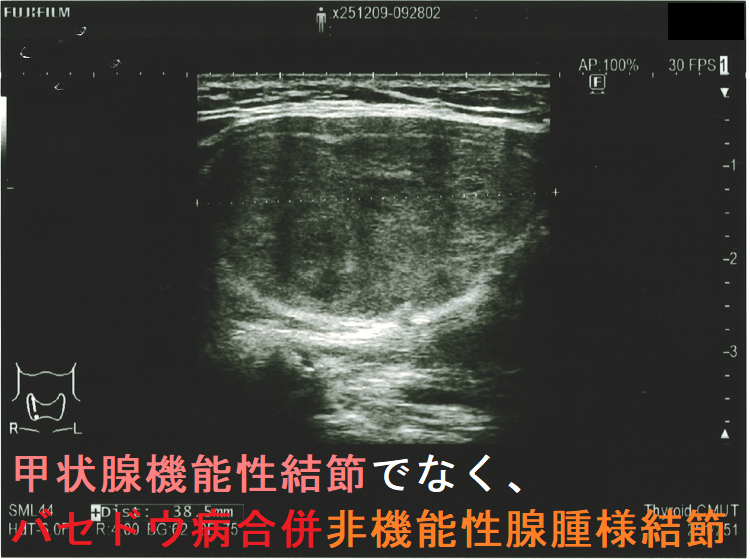

- 甲状腺機能性結節(機能性甲状腺腫)でなく、バセドウ病合併非機能性腺腫様結節だった

超音波(エコー)検査

機能性結節の74.1% は結節内および周辺の血流が豊富ですが、25.9%は周辺の血流のみが豊富です[Radiol Med. 1998 Mar;95(3):193-8.]。